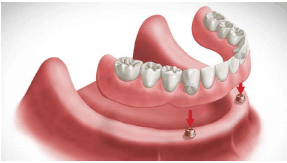

Sobre a especialidade de prótese dentária, identifique a seguinte reabilitação oral da imagem apresentada.

Provas